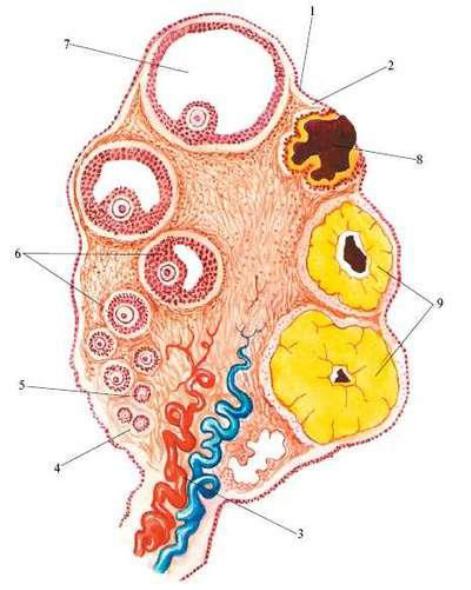

Созревание фолликула в яичнике: этапы и процессы